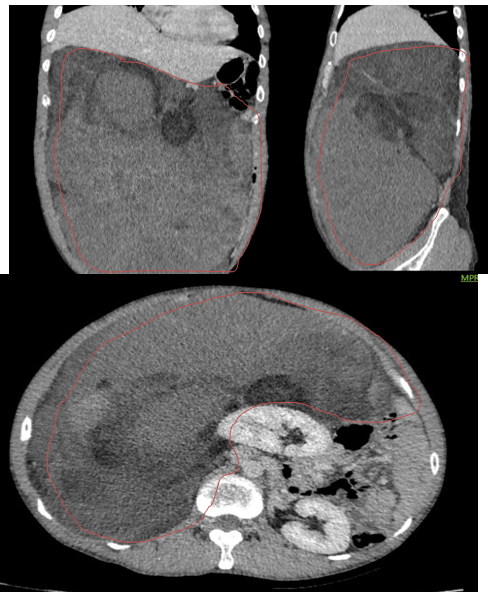

- Xquang ngực: Vòm hoành phải bị đẩy lên cao, dải xẹp phổi mảnh đáy phổi phải.

Hình 1. Hình ảnh chụp XQ ngực thẳng: vòm hoành phải bị đẩy lên cao do u chèn ép (mũi tên đỏ).